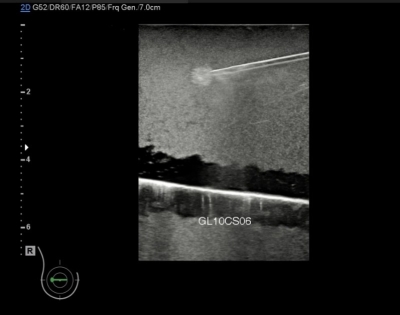

• ให้ภาพอัลตราซาวด์ของเข็มเจาะชัดเจน

• สามารถใช้ซ้ำเนื่องจากวัสดุมีคุณสมบัติซ่อมแซมตัวเองได้